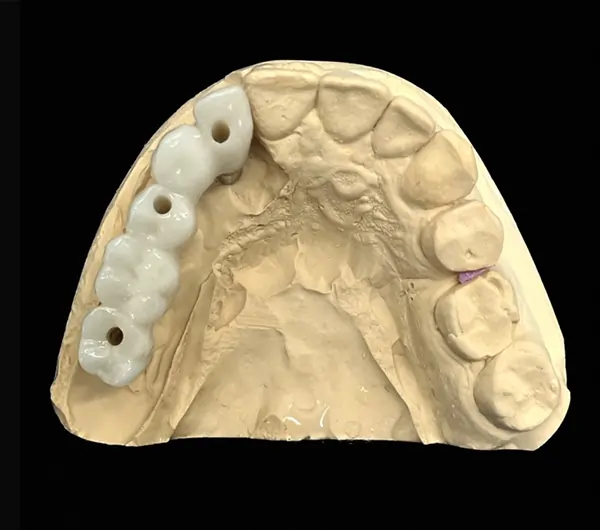

Zirconia Screw Retained Implant Crown to Ti-Base restorations are preferred by dentists for their ease of replacements and cleanings. Designed for both single and multiple unit restorations, implant solutions remain the best way to prevent bone loss while providing a comfortable restoration experience for the patient and maintaining facial structure aesthetics. Our Screw Retained Zirconia Crowns are compatible with most systems.

A PFM Non Precious Screw Retained Implant Crown is a great solution for dentists who prefer screw retained restorations and are looking for the most economical way to restore an implant. These are cemented on to a Ti-Base.

Full Arch Zirconia implant-retained restorations are ideal for patients seeking superior aesthetics and durability than ordinary acrylic dentures. They are optimal for those with a strong bite, grind, or damage from previous restorations.